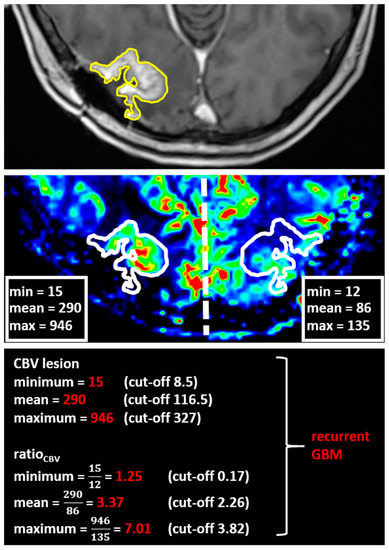

Using the MCEval ROI (region of interest) tool of the mean curve plug-in of MR neurology, two ROIs were manually placed by a neuroradiologist (authors F.E. and M.A.S.) on the image slice depicting the largest lesion diameter in the co-registered MPRAGE x DSC map: a selective ROI in the contrast-enhancing lesion area with the highest CBV value excluding vessels and nontumorous tissue, and an unselective ROI contouring the whole contrast enhancing lesion including necrotic or cystic areas. Then, both ROIs were copied onto the corresponding ADC map. A third ROI was placed in the co-registered CBV perfusion and ADC maps in the contralateral healthy white matter excluding vessels, cerebrospinal fluid, and bone. Figure 1 and Figure 2 show exemplary measurements in a patient with recurrent GBM and a patient with TRC. Image post-processing and manual ROI placement took approximately 4 min.

Figure 1. Exemplary cerebral blood volume and apparent diffusion coefficient measurements in a patient with recurrent glioblastoma. Exemplary apparent diffusion coefficient (ADC) measurement of a selective region of interest (ROI) (red) in the contrast-enhanced area with the highest cerebral blood volume (CBV) and an unselective ROI (yellow) comprising the whole contrast-enhancing lesion in a patient with recurrent glioblastoma (GBM). After placing the ROIs carefully in the fused CBV x contrast-enhanced T1 sequence map, ROIs are copied to the exact same position in the corresponding ADC map.

Figure 5. Exemplary application of the computed cerebral blood volume thresholds in the clinical routine to differentiate recurrent glioblastoma and treatment-related changes. A 60-year-old patient with a new contrast-enhancing lesion in the right occipital lobe (upper line) after radical resection and combined radiochemotherapy of a GBM. First, the whole contrast-enhancing lesion is contoured, then copied to the exact same position in the corresponding CBV map (middle). A second ROI is placed in the contralateral healthy hemisphere mirrored along the midline (falx cerebri). Applying our algorithm, we concluded the new lesion to be recurrent GBM (basal line). A biopsy confirmed the radiologic diagnosis.